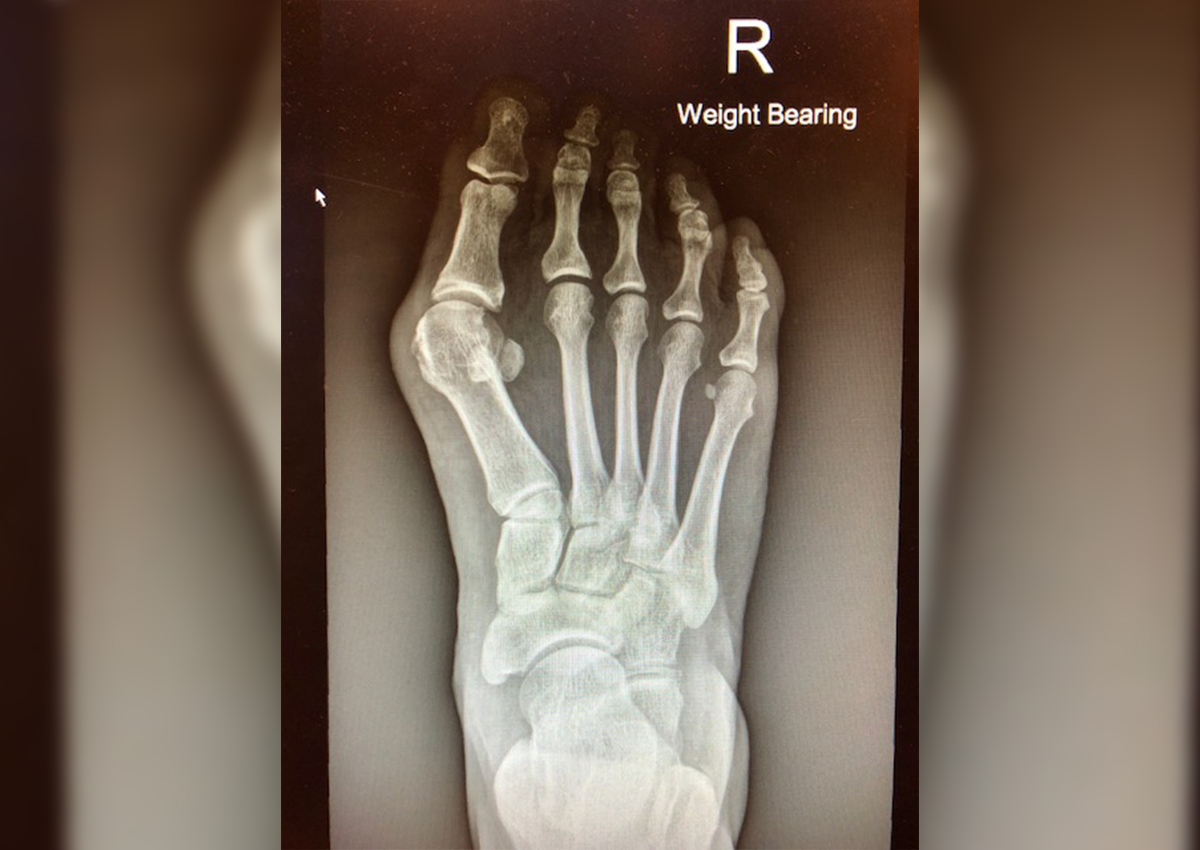

Bunions are a foot deformity of the joint and bone in the big toes, making the bones protrude. In serious cases, the toes overlap, making it painful to wear covered shoes.

For bunions that aren't too serious, there are toebox shoes and silicone bunion shields to help prevent and stop the deformity at an early stage.